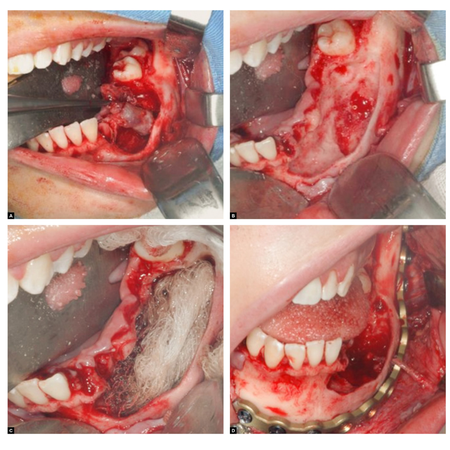

Introduction: Facial malignancies treated with surgery usually result in significant anatomical defects. Titanium is the gold standard, but its high cost limits accessibility. PMMA emerges as a cost-effective alternative, with good efficacy when associated with 3D planning. Case report: A patient, who underwent maxillectomy and radiotherapy 4 years prior for squamous cell carcinoma of the palate, presented with an extensive maxillary defect. 3D planning, stereolithography with ABS polymer, and a custom-made PMMA implant molded in a muffle were utilized. The surgical approach was via a...

Introduction: Facial malignancies treated with surgery usually result in significant anatomical defects. Titanium is the gold standard, but its high cost limits accessibility. PMMA emerges as a cost-effective alternative, with good efficacy when associated with 3D planning. Case report: A patient, who underwent maxillectomy and radiotherapy 4 years prior for squamous cell carcinoma of the palate, presented with an extensive maxillary defect. 3D planning, stereolithography with ABS polymer,...